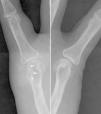

The ultrasound showed no effusion, but found a soft tissue injury, partially defined, and heterogeneous echotexture with hyperechoic areas. The tumor was in contact with the cortical bone of the metacarpal, which remained intact, except for an area where we observed a marked erosion, with a soft tissue lesion projecting into the medullary cavity (Fig. 1). Given the ultrasonography findings, X-rays were analyzed, confirming increased periarticular soft tissues, with very high density, accompanied by erosion of the metacarpal head, which as a hallmark had a sclerotic margin (Fig. 2). These sonographic and radiographic findings indicated periarticular tophi associated with bone erosion. The ultrasound-guided arthrocenthesis of the tophus showed a dense whitish material that under polarized light microscopy was identified as monosodium urate crystals (Fig. 3).

X-rays centered on the fifth metacarpophalangeal joint of both hands that allows for the assessment of the bone erosion comparatively and shows the sclerotic margin (arrows) with soft tissue augmentation and high density in the medial aspect of the right metacarpal head. There was no involvement of the joint space.